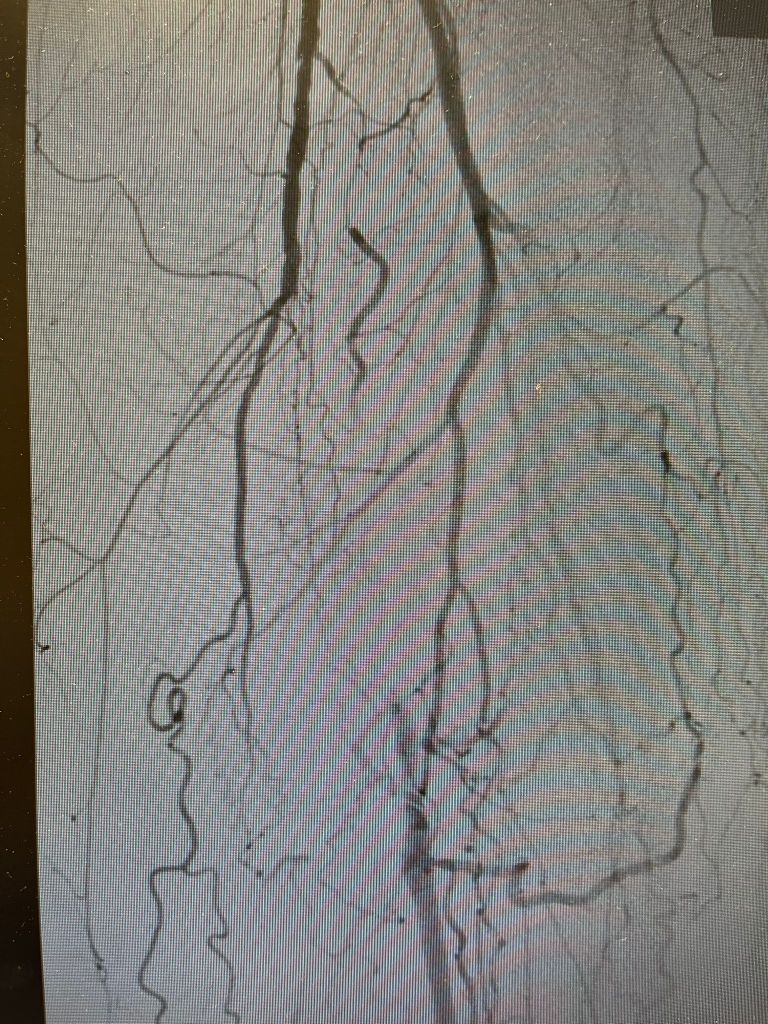

Der gleiche Patient, nachdem die Schlagader mit einer Gefäßfräse wieder eröffnet wurde